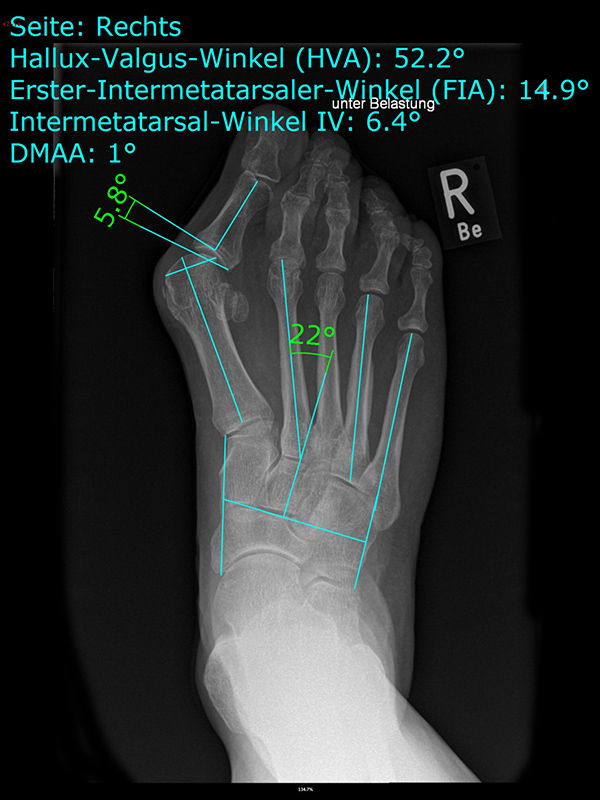

• Folgende Winkel können präoperativ zur Erleichterung der Planung am Röntgenbild eingezeichnet werden:

• IMW (Intermetatarsalwinkel).

• HVW (Hallux valgus-Winkel).

• DMAA (Distal Metatarsal Articular Angle) – Planung der ggf. notwendigen Reverdin-Isham-Osteotomie.

• PPAA (Proximal Phalangeal Articular Angle) – Planung der ggf. notwendigen Akin-Osteotomie.

• VAW (Vorfußadduktionswinkel) – Planung der Ausrichtung der DMMO (Distalen minimalinvasiven Metatarsale Osteotomien).

Einschränkend ist anzumerken, dass o.g. Winkel projektions- und rotationsabhängig sind 15. Daher ist intraoperativ die Planung anhand von Bildverstärkeraufnahmen zu verifizieren und ggf. anzupassen.

Zum Lesen der Bildbeschreibung und zur Vollansicht bitte das Bild anklicken.

In unserer prospektiven Studie wurden 10 Patienten (8 Frauen und 2 Männer; Ø Alter 58 ¼ Jahre) mit einem symptomatischen Hallux valgus bei Pes adductus und Metatarsalgie mittels einer Lapidusarthrodese und einer lateralisierenden DMMO versorgt. Die Fusion des TMT-I-Gelenkes erfolgte offen mittels einer winkelstabilen, plantaren Platte. Alle zusätzlichen distalen Eingriffe (DMMO, Isham-OT, Akin-OT, Kleinzehenkorrekturen) wurden in minimalinvasiver Technik durchgeführt. Die Patienten wurden nach 6 Monaten klinisch und radiologisch nachuntersucht.

Der präoperative AOFAS-Score betrug 41,5 Punkte und konnte postoperativ auf durchschnittlich 86,2 Punkte verbessert werden (p<0,005). Der IMW reduzierte sich von Ø 16,7° (8,5°-20,3°) präoperativ auf Ø 7,14° (6,1°-9,5°) (p<0,005). Ebenso konnte der HVW von präoperativ Ø 45,2° auf postoperativ Ø 9,4° (p<0,005) korrigiert werden. Durch die Durchführung der modifizierten, lateralisierenden DMMO veränderte sich der präoperative VAW von Ø 23° (19,3°-33,5°) auf Ø 15,6° (13°-17,2°; p<0,004).